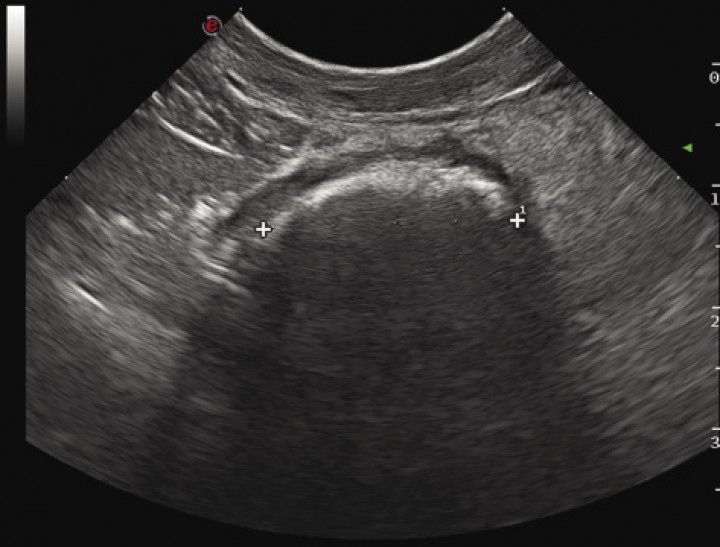

Para corroborar el diagnóstico presuntivo de obstrucción intestinal mecánica se procedió a la realización de una ecografía de abdomen en la que se observó distensión de varias asas intestinales sin motilidad y contenido ecogénico; en el interior de un asa de yeyuno se apreció una estructura hiperecogénica de al menos 4 cm de longitud con una marcada sombra acústica (Fig. 3). También se observó el peritoneo levemente hiperecogénico en la región adyacente al asa que contenía la sombra acústica, y los linfonodos yeyunales se observaban con ecotextura heterogénea y levemente aumentados de tamaño.

<p>Imagen ecográfica del asa intestinal con presencia de una estructura hiperecogénica con marcada sombra acústica en su interior.</p>

Imagen ecográfica del asa intestinal con presencia de una estructura hiperecogénica con marcada sombra acústica en su interior.

Estos hallazgos eran compatibles, más probablemente, con un cuerpo extraño, peritonitis o esteatitis focal leve y linfadenopatía reactiva, aunque también podía deberse, con menor probabilidad, a la hiperplasia de los linfonodos yeyunales debido a la edad del paciente.